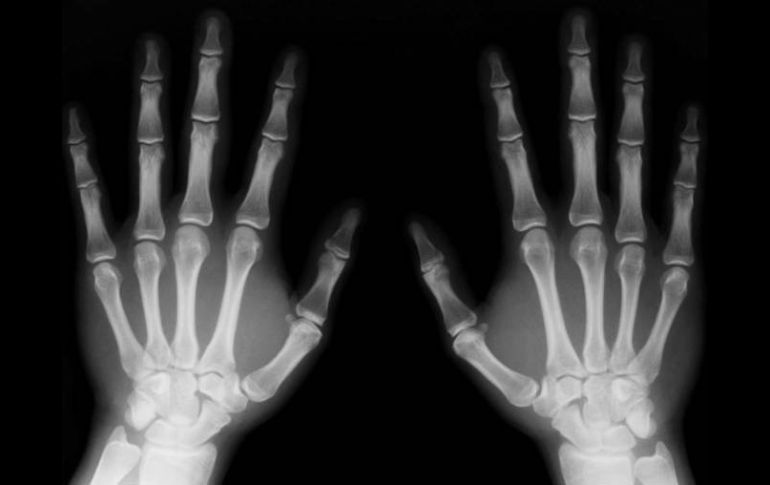

Según la investigación, la vitamina E destruye más hueso del que se crea. ESPECIAL  /

LONDRES, INGLATERRA (05/MAR/2012).- Los suplementos de vitamina E podrían perjudicar al mantenimiento de los huesos, según un estudio realizado por científicos japoneses que recoge hoy la revista británica "Nature Medicine".

La cantidad de masa ósea está determinada por el equilibrio entre dos tipos de células: los osteoblastos, que intervienen en la creación del nuevo tejido óseo, y los osteoclastos, que lo degradan.

En la investigación japonesa, los ratones con dosis altas de vitamina E perdieron masa ósea, un dato que los científicos consideran que se debe a que este componente aumenta el número de osteoclastos, lo que a su vez se traduce en que se destruye más hueso del que se crea.

Los investigadores subrayaron que, aunque estos resultados podrían ser importantes para prevenir el riesgo de fracturas en un futuro, es necesaria una investigación más profunda en humanos.